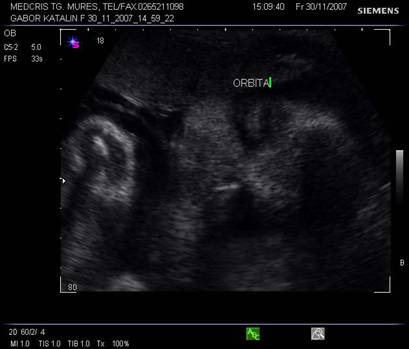

Planul XIII - indica simultan orbitele si regiunea mandibulara, cristalinul apare ca un inel ecogenic in partea anterioara a orbitelor. Miscarile lente sau rapide ale ochilor pot fi cateodata evidentiate.

Planul XIV - plan oblic pentru orbite si nas.